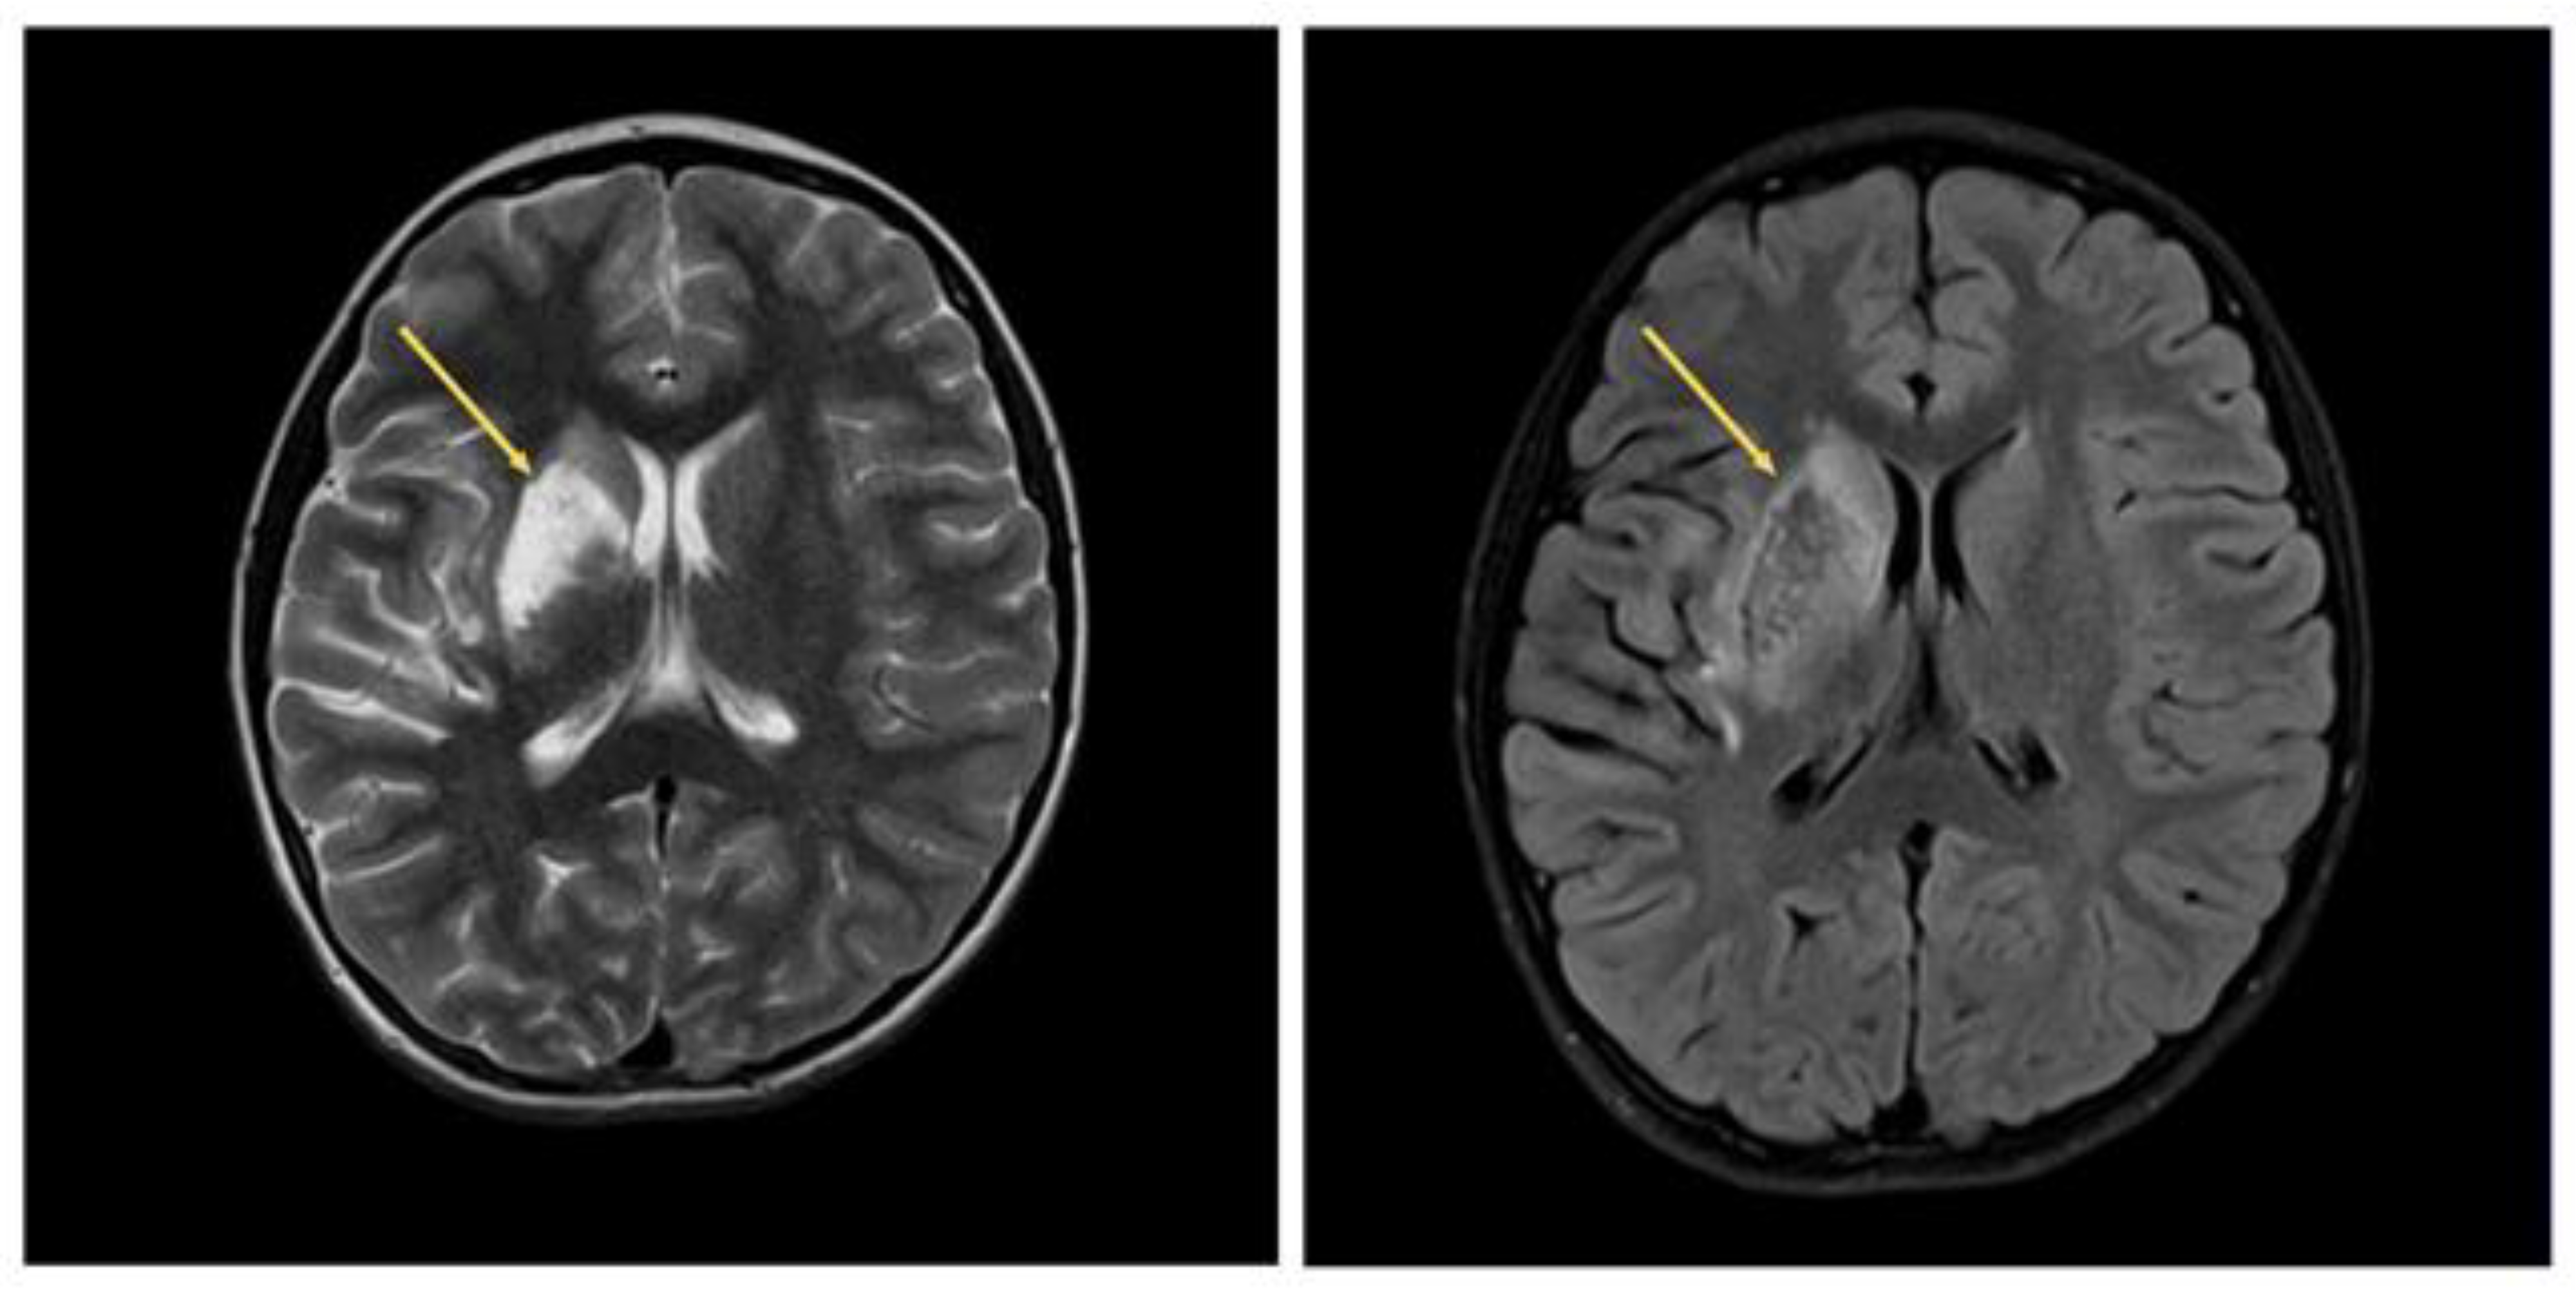

2. Case 1

2.1. Examination Data

2.2. Substantiation of Diagnosis

3. Case 2